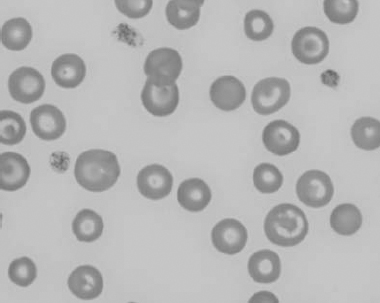

Figure 1.3 Canine blood film showing acanthocytes (also see color section).

Figure 1.4 Canine blood film showing anisocytosis (also see color section).

Figure 1.5 Bovine blood film showing basophilic stippling within a macrocyte as part of the regenerative response (also see color section).

Figure 1.6 Canine blood film showing basophilic stippling due to lead toxicosis (also see color section).

Figure 1.7 Canine blood film showing blister cells due to oxidative damage (also see color section).

Figure 1.8 Canine blood film showing codocytes. Up to 50% codocytes may be normal in a dog (also see color section).

Figure 1.9 Canine blood film showing eccentrocytes due to oxidative damage (also see color section).

Figure 1.10 Canine blood film showing echinocytes I (also see color section).

Figure 1.11 Canine blood film showing echinocytes III (also see color section).

Figure 1.12 Feline blood film showing echinoelliptocytes (also see color section).

Figure 1.13 Canine blood film showing Heinz bodies and ghost cells due to oxidative damage. There are also several polychromatophils (also see color section).

Figure 1.14 Canine blood film stained with new methylene blue, to demonstrate Heinz bodies (also see color section).

Figure 1.15 Canine blood film showing keratocytes and schizocytes (erythrocyte fragments) due to fibrin strand injury. A codocyte and a polychromatophil also appear in the field (also see color section).

Figure 1.16 Feline blood film showing Mycoplasma hemofelis organisms (hemobartonellosis). Organisms are not always visible in blood smears from infected cats (also see color section).

Figure 1.17 Canine blood film showing several macrocytes (also see color section).

Figure 1.18 Canine blood film showing a metarubricyte There is also a polychromatophilic macrocyte in the field (also see color section).

Figure 1.19 Canine blood film showing microcytic, hypochromic erythrocytes consistent with iron deficiency anemia. There are two polychromatophils in the field, indicating that the anemia is regenerative (also see color section).

Figure 1.20 Canine blood film showing two macrocytes with nuclear remnants (also see color section).

Figure 1.21 Bovine (calf) blood film showing marked poikilocytosis (normal?) (also see color section).

Figure 1.22 New methylene-blue-stained Canine blood film showing reticulocytes (also see color section).

Figure 1.23 Canine blood film showing rouleaux formation (also see color section).

Figure 1.24 Canine blood film showing spherocytosis and polychromasia due to immune-mediated hemolytic anemia (also see color section).

Figure 1.25 The red blood cell cytoskeleton.